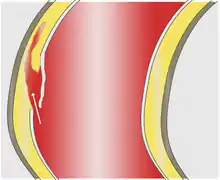

In an aortic dissection, blood penetrates the intima and enters the media layer. The high pressure rips the tissue of the media apart along the laminated plane splitting the inner two-thirds and the outer one-third of the media apart.[17] This can propagate along the length of the aorta for a variable distance forward or backwards. Dissections that propagate towards the iliac bifurcation (with the flow of blood) are called anterograde dissections and those that propagate towards the aortic root (opposite of the flow of blood) are called retrograde dissections. The initial tear is usually within 100 mm of the aortic valve, so a retrograde dissection can easily compromise the pericardium leading to a hemopericardium. Anterograde dissections may propagate all the way to the iliac bifurcation of the aorta, rupture the aortic wall, or recanalize into the intravascular lumen leading to a double-barrel aorta. The double-barrel aorta relieves the pressure of blood flow and reduces the risk of rupture. Rupture leads to hemorrhaging into a body cavity, and prognosis depends on the area of rupture. Retroperitoneal and pericardial ruptures are both possible.

The initiating event in an aortic dissection is a tear in the intimal lining of the aorta. Due to the high pressures in the aorta, blood enters the media at the point of the tear. The force of the blood entering the media causes the tear to extend. It may extend proximally (closer to the heart) or distally (away from the heart) or both. The blood travels through the media, creating a false lumen (the true lumen is the normal conduit of blood in the aorta). Separating the false lumen from the true lumen is a layer of intimal tissue known as the intimal flap.

The vast majority of aortic dissections originate with an intimal tear in either the ascending aorta (65%), the aortic arch (10%), or just distal to the ligamentum arteriosum in the descending thoracic aorta (20%).

As blood flows down the false lumen, it may cause secondary tears in the intima. Through these secondary tears, the blood can re-enter the true lumen.